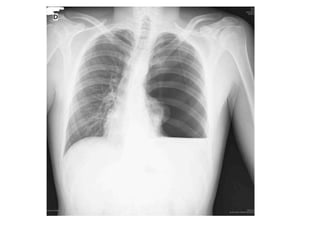

Derrame pleural tipico

neumotorax